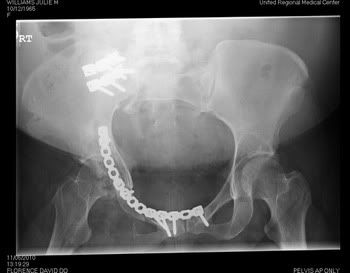

Most people don't understand why I am the way I am. I hope these x-rays give them a better idea of what I have to deal with every single day.

My hip and pelvis